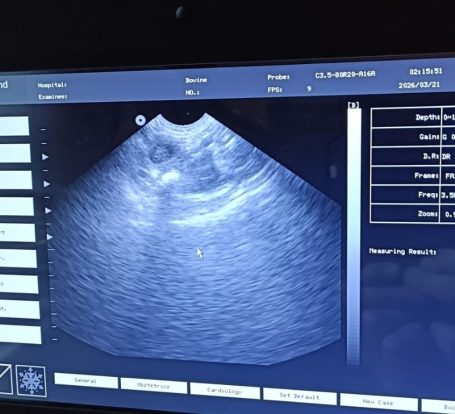

Kato heeft de echo gehad. Die hebben we hier thuis gemaakt. We hebben helaas slechts 2 pupjes kunnen vinden. Hopelijk ligt het aan de echo en zitten er een paar meer in haar buikje. Nu is het afwachten tot we de röntgenfoto laten maken half april. En natuurlijk wachten op de bevalling rond 25 april.